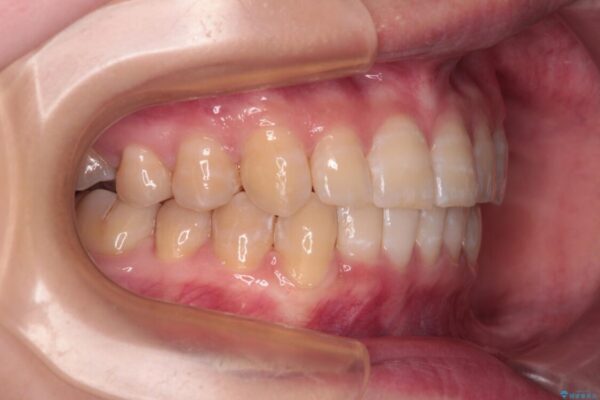

下顎の八重歯を気にして来院された患者様です。

下顎前歯にデコボコが集中していたため、顎間ゴムによる後方移動とIPR(歯と歯の間を削ること)により歯列を整えることとしました。

治療前、下顎前歯のデコボコが集中しており、奥歯の咬み合わせは、上顎に対して下顎が前方位にある状態でした。下顎の歯列を後方へ移動させる治療はインビザラインの得意とするところですので、1年程度で無事に治療を終えることができました。

• 【モニター】下顎前歯のデコボコをインビザラインできれいに 治療前画像